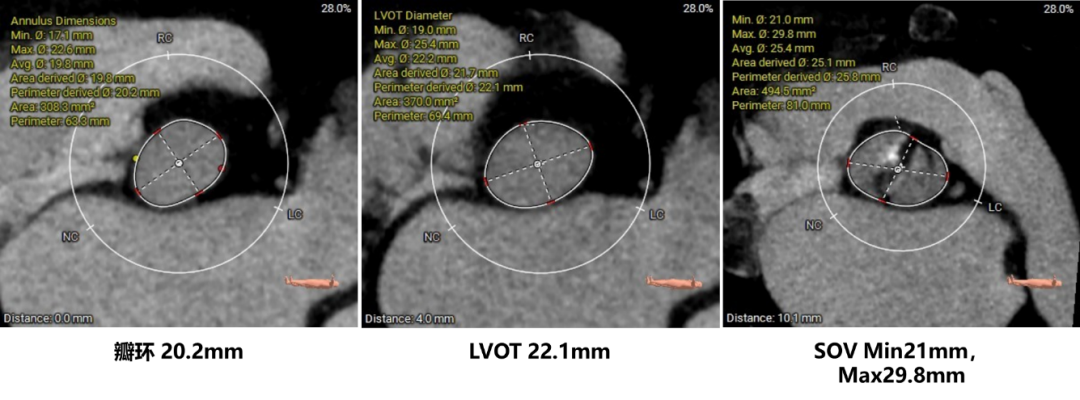

主动脉根部评估:

瓣环上结构测量: